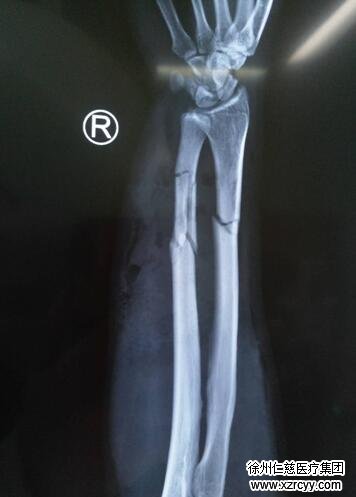

小张拍完片子后,X片上显示右尺骨远段粉粹性骨折,右桡骨远段骨折,且右前臂肿胀非常厉害,皮肤隐隐约约出现了一些细微的花斑。因为剧烈疼痛,小张在急诊清创室内一直忍不住大喊:“痛死了,痛死了......医生快救救我!”

各项检查完毕后,手术室内,由于右臂异常肿胀,小张的右前臂切开后创面就像熟透的西瓜炸裂一样难以缝合。“我们首先对他进行了切开减压与清创,然后修复了损坏的血管与神经,因为患者右尺桡骨骨折,我们复位后给患者进行了外固定支架固定。患者后期还需皮瓣修复创面,他的前臂皮肤软组织缺损面积较大。”黎医生说。